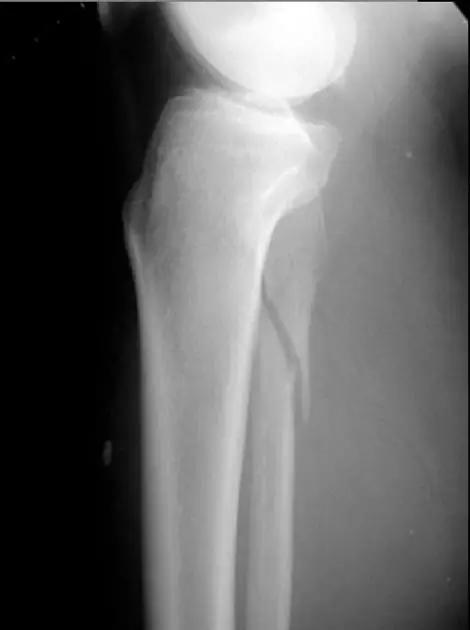

5. Maisonneuve 骨折

腓骨近端骨折伴内踝骨折及三角韧带断裂。

(来源:Radiopaedia)